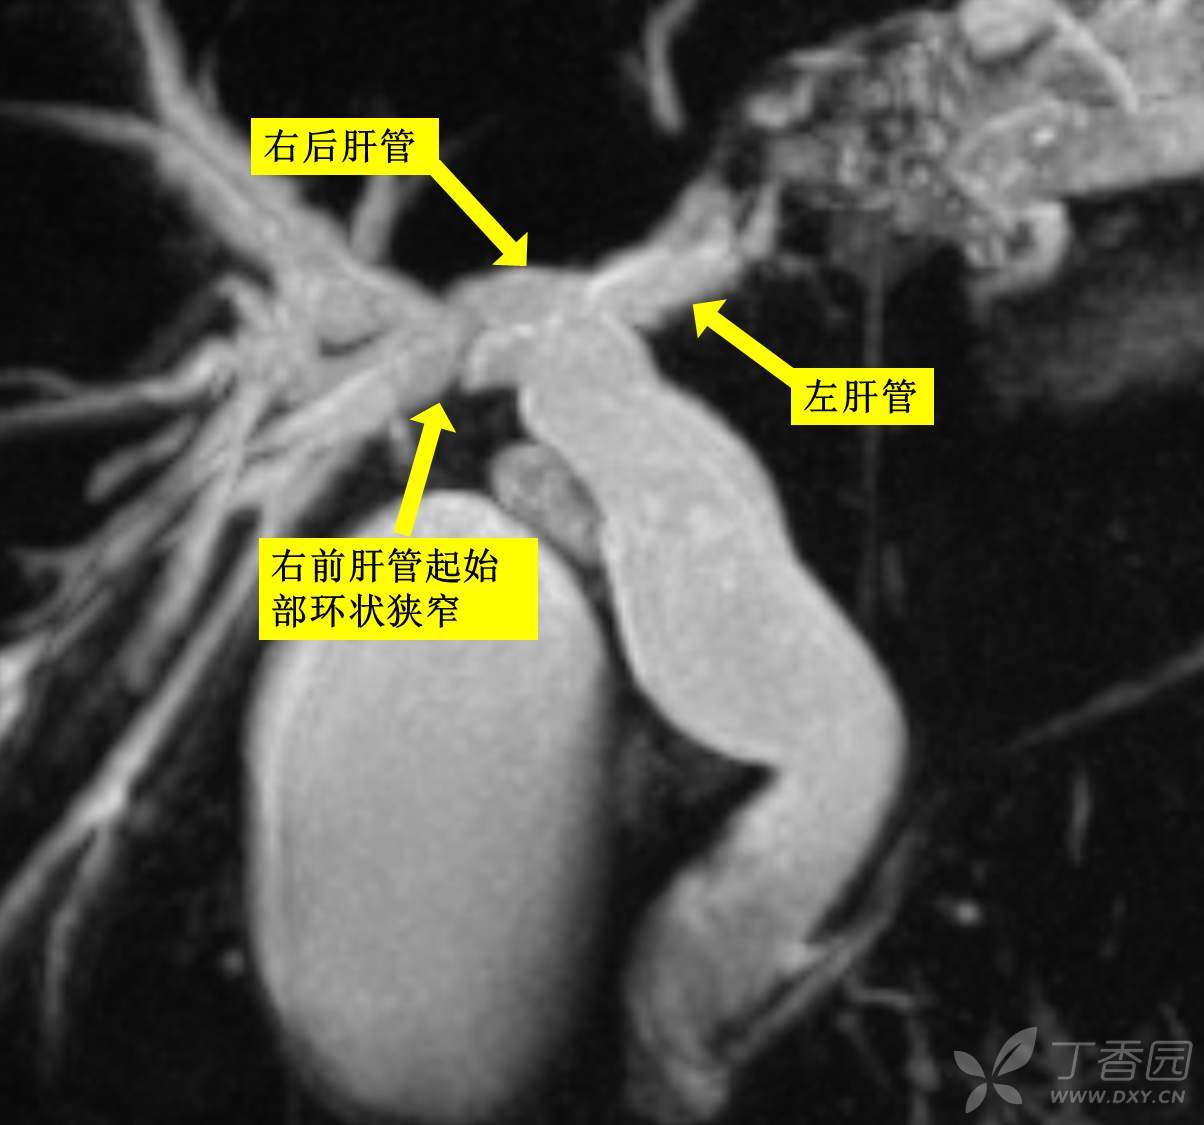

第三步:做胆肠。有几个关键点是我没想到的,1.右前肝管有狭窄环,必须在此上面离断。(me:直到打开狭窄环我才想起“胆管囊肿往往有狭窄环”这句教科书上说的金句,很多医生因此而掉坑,而主刀在术前片子上就看到了,如下图)

(me:切完狭窄环,我以为找到了右前右后肝管,主刀又说我又错了,那个只是8段和5段肝管,真正的右后肝管是和左肝管先汇合的,这个人有解剖变异,汗颜!又差点掉坑里)

手术结束后,经主刀W教授讲解,反过头再看片子,如图